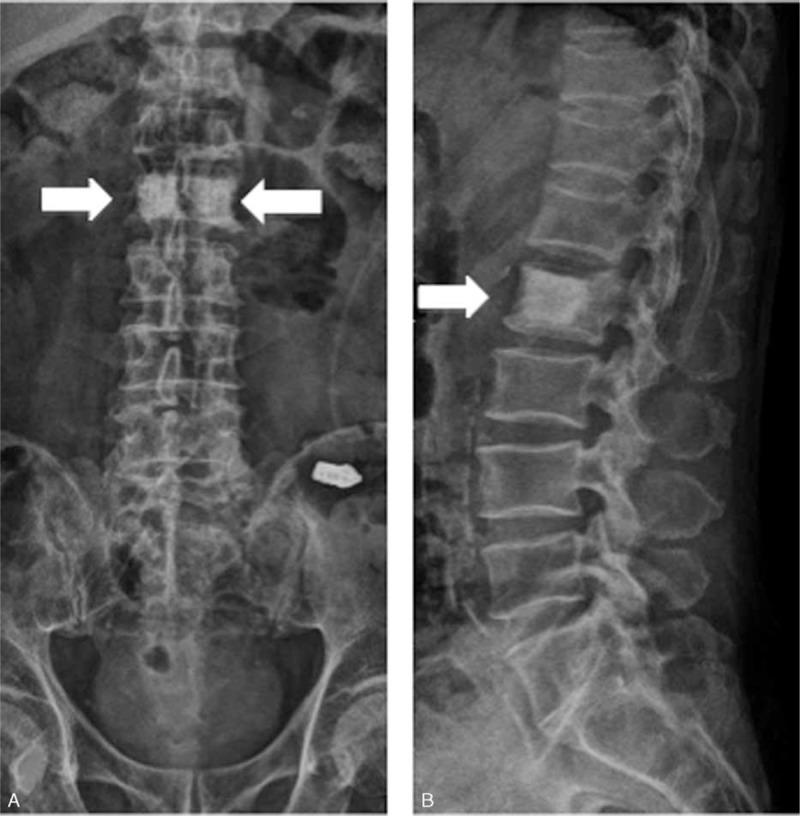

Compression fracture of the vertebral body is common in the older patients. The possible etiology like osteoporosis or cancer metastasis should be included as a possibility in the differential diagnosis for severe back pain, to prevent delays in diagnosis and treatment. More severe fractures can cause significant pain, leading to inability to perform activities of daily living, and life-threatening in the older patient.We report a rare case of a 61-year-old man suffering from severe lower back pain and intermittent abdominal fullness. He came to our clinic, where muscle power was normal, but could not stand up or change posture because of severe back pain. Plain film and magnetic resonance imaging of lumbar spine both revealed osteoblastic lesion at L2 spine. Abdomen computed tomography showed a mass at the pancreatic body. The pancreatic cancer with osteoblastic metastasis was diagnosed. After receiving multimodality therapy such as percutaneous vertebroplasty and pain controlling, we provided effective palliation of symptoms, aggressive rehabilitation program, and better quality of life.Our case highlights the benefits of multidisciplinary cancer treatment for such patient, preventing the complications such as immobilization accompanied with adverse effects like musculoskeletal, respiratory, and cardiovascular systems. All clinicians should be informed of the clinical findings to provide patients with suitable therapies and surveys.

椎体压缩性骨折在老年患者中很常见。在严重背痛的鉴别诊断中,应将骨质疏松症或癌症转移等可能的病因考虑在内,以防止诊断和治疗延误。更严重的骨折会导致严重疼痛,导致老年患者无法进行日常生活活动,甚至危及生命。我们报告一例罕见病例,一名61岁男性,患有严重的下背痛和间歇性腹胀。他来到我们诊所,肌肉力量正常,但由于严重背痛无法站立或改变姿势。腰椎X线平片和磁共振成像均显示L2椎体有成骨病变。腹部计算机断层扫描显示胰体有一个肿块。诊断为胰腺癌伴成骨转移。在接受了经皮椎体成形术和疼痛控制等多模式治疗后,我们有效缓解了症状,实施了积极的康复计划,并改善了生活质量。我们的病例强调了多学科癌症治疗对这类患者的益处,预防了诸如因肌肉骨骼、呼吸和心血管系统等不良反应而导致的固定不动等并发症。所有临床医生都应了解这些临床发现,以便为患者提供合适的治疗和检查。